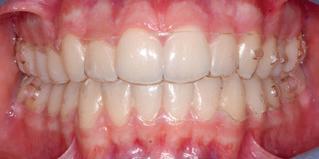

tory outcome after four months of CMA with fulltime Class II elastic wear and eight months of clear aligner therapy (Fig. 5). The patient showed an esthetic profile and incisor display on smiling, along with a Class I canine and molar relationship. The midlines were centered and the crowding was resolved, but the second molar occlusal contacts were less than optimal, probably because of the presence of a palatal precontact.